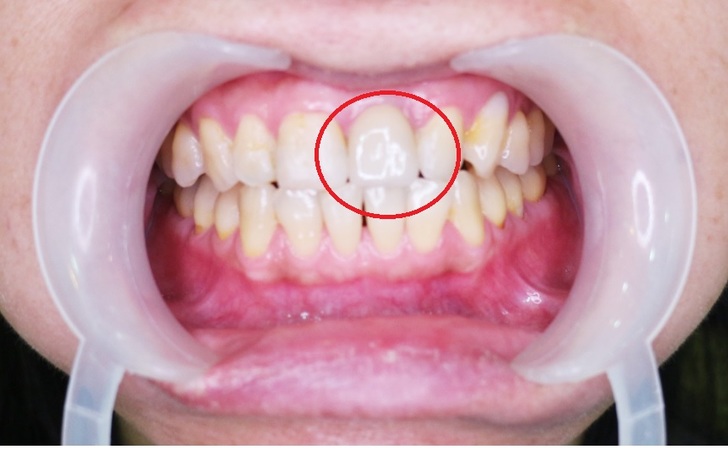

他也是替我做門牙微創植牙的手術醫師

會興起做植牙念頭主要是門牙做過根管治療

門牙做完根管治療後戴著保護用牙套已近十年

平日吃飯後雖有定期刷牙清潔

但依舊免不了牙菌斑侵襲造成牙根損傷

即使時常刷牙卻還是容易有輕微口臭

朱醫師為我拆下牙套後裡面牙根已爛得不像話

難怪就連有固定刷牙還是有口臭問題存在

看著爛到不行的牙根毅然決然請朱醫師盡快為我安排時間植牙